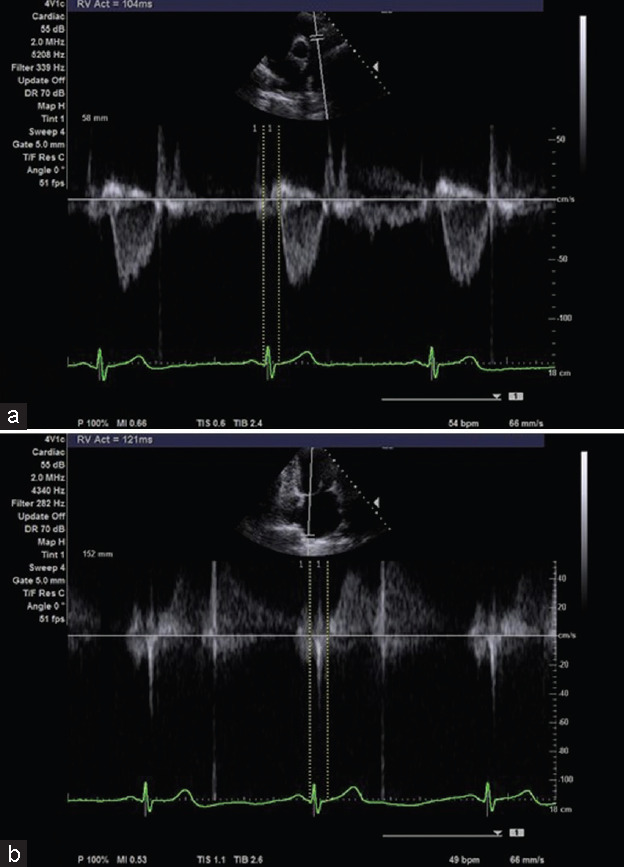

Objective: The objective of this study was to assess pulmonary arterial hemodynamics using pulmonary pulse transit time (pPTT) following balloon mitral valvuloplasty (BMV).

Patients and methods: Thirty-three patients with moderate-to-severe mitral stenosis (MS) with varying pulmonary hypertension degree who were presented to the National Heart Institute to do percutaneous mitral balloon valvuloplasty. Participants were evaluated for their echocardiographic variables including the pPTT, and they were followed up immediately, 1 week, 1 month, and 6 months after BMV.

Results: The study demonstrated a significant and progressive improvement in the right ventricular fractional area change and the tricuspid annular plane systolic excursion (TAPSE) following BMV; on the other hand, the pulmonary artery systolic pressure demonstrated a significant decrease postprocedure and during the follow-up period. On analysis, we found a significant change observed in pPTT values postprocedure (P < 0.001). This value showed a significant reduction immediately following the procedure and the decline continued over the subsequent follow-up periods. Each of these postprocedure measurements showed a significant decrease from the baseline (P < 0.001).

Conclusion: The pPTT was high in postcapillary pulmonary hypertension (in MS patients) and reduced after correction of causative pathology; the pPTT is a valid measure to assess the improvement in PAH after BMV.